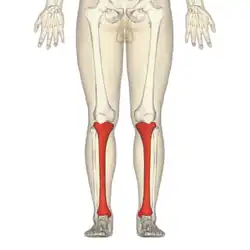

Schienbein

Das Schienbein (lateinisch Tibia) ist neben dem Wadenbein (Fibula) einer der beiden Knochen des Unterschenkels. Das Schienbein ist der kräftigere der beiden Knochen und ein typischer Röhrenknochen. Das lateinische Wort tibia ist die Bezeichnung einer Knochenflöte und der lateinische Name des in der griechischen Antike als Aulos bekannten Blasinstruments.